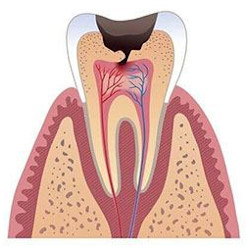

Пульпит подрузумевает воспаление тканей нервов и сосудов полости зуба. Проявляется острой (стреляющей) болью. Чаще всего пульпит является следствием запущенного (нелеченного вовремя) кариеса.